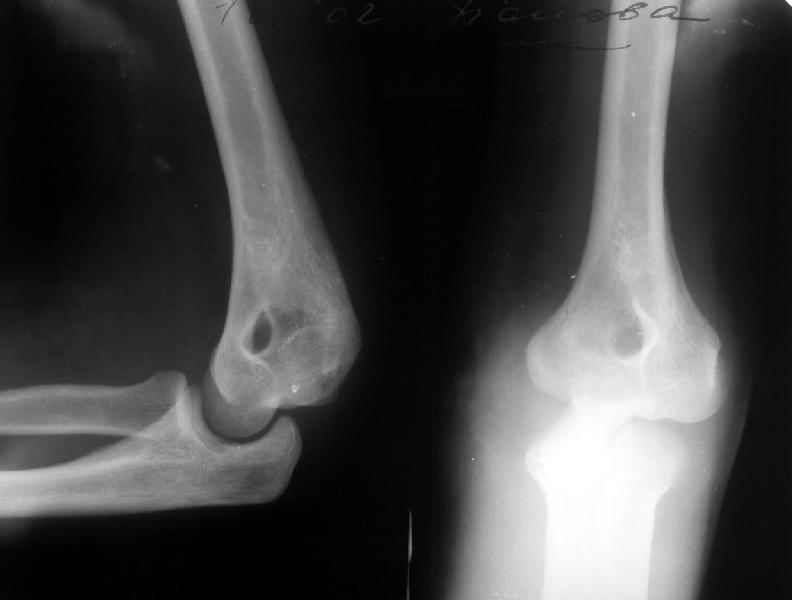

Пациентка 48 лет при падении с 5 этажа получила травму 28.04.02. Среди прочих повреждений был открытый задний вывих предплечья (см. снимок). Он был сразу вправлен, рана 6 см по внутренней поверхности

области локтевого сустава была обработана по месту первичного поступления. К нам поступила 7.05.02. Рана зажила первичным натяжением. Вчера, то есть через три недели после вправления, сняли повязку для разработки движений. Выявлено, что предплечье легко смещается медиально, и вправляется. Движения в локтевом суставе пока плохие. Свежие снимки и в правильном положении, и в подвывихе прилагаются. Вопрос - что делать? Продлить иммобилизацию гипсом? Идти на ревизию и восстановление внутренней боковой связки? Наложить шарнирный аппарат? Заранее спасибо. -- Best regards, Alexander N. Chelnokov